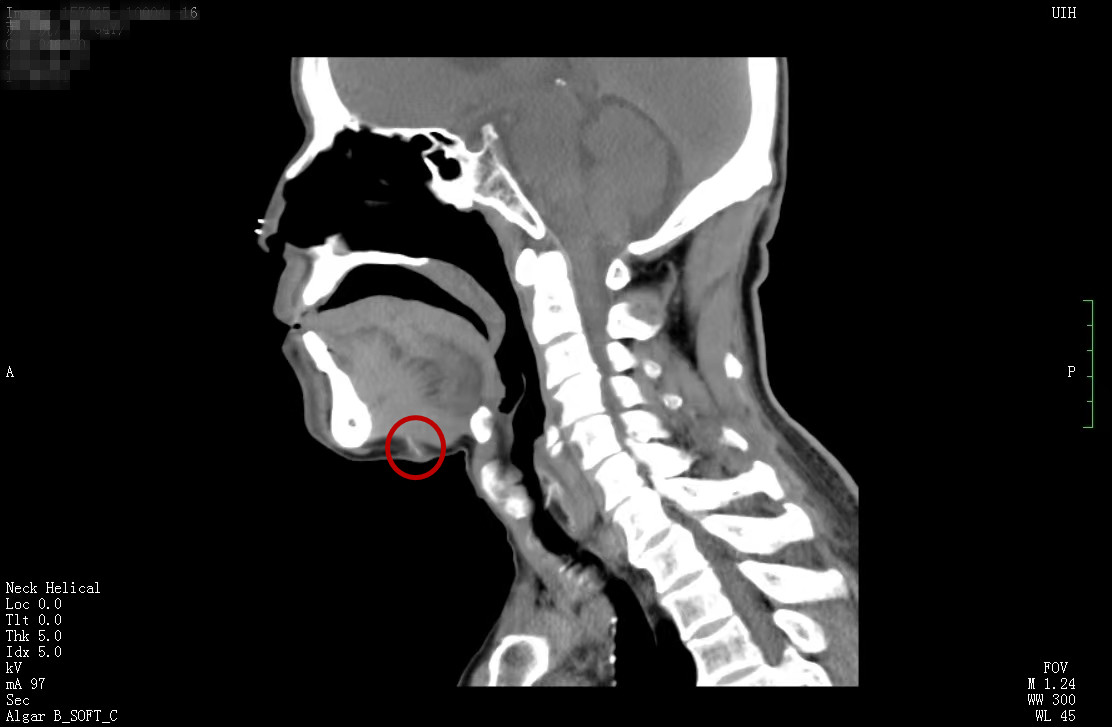

苏先生到医院就诊时,医生结合检查结果和仔细询问,考虑其脖子上的包块可能与异物有关,但苏先生一再否认。为查清病因,耳鼻喉三病区副主任周建波为其实施了手术探查,发现一根2-3cm的鱼刺,一端还有分叉。苏先生仔细看了这根鱼刺后,才想起4个月前喝鱼汤时卡过一次鱼刺,当时吞了几口白米饭,感觉已经咽下去了,就没有过多重视,没想到它跑到了脖子上。经过手术,苏先生恢复良好,于5月13日出院。

周建波副主任介绍,鱼刺卡喉是耳鼻喉科常见的急症,但像苏先生这样,鱼刺从舌根穿到颈部,不仅毫无症状,还“嬗变”成了一个包块,比较罕见,所幸没有刺破大血管而危及生命。